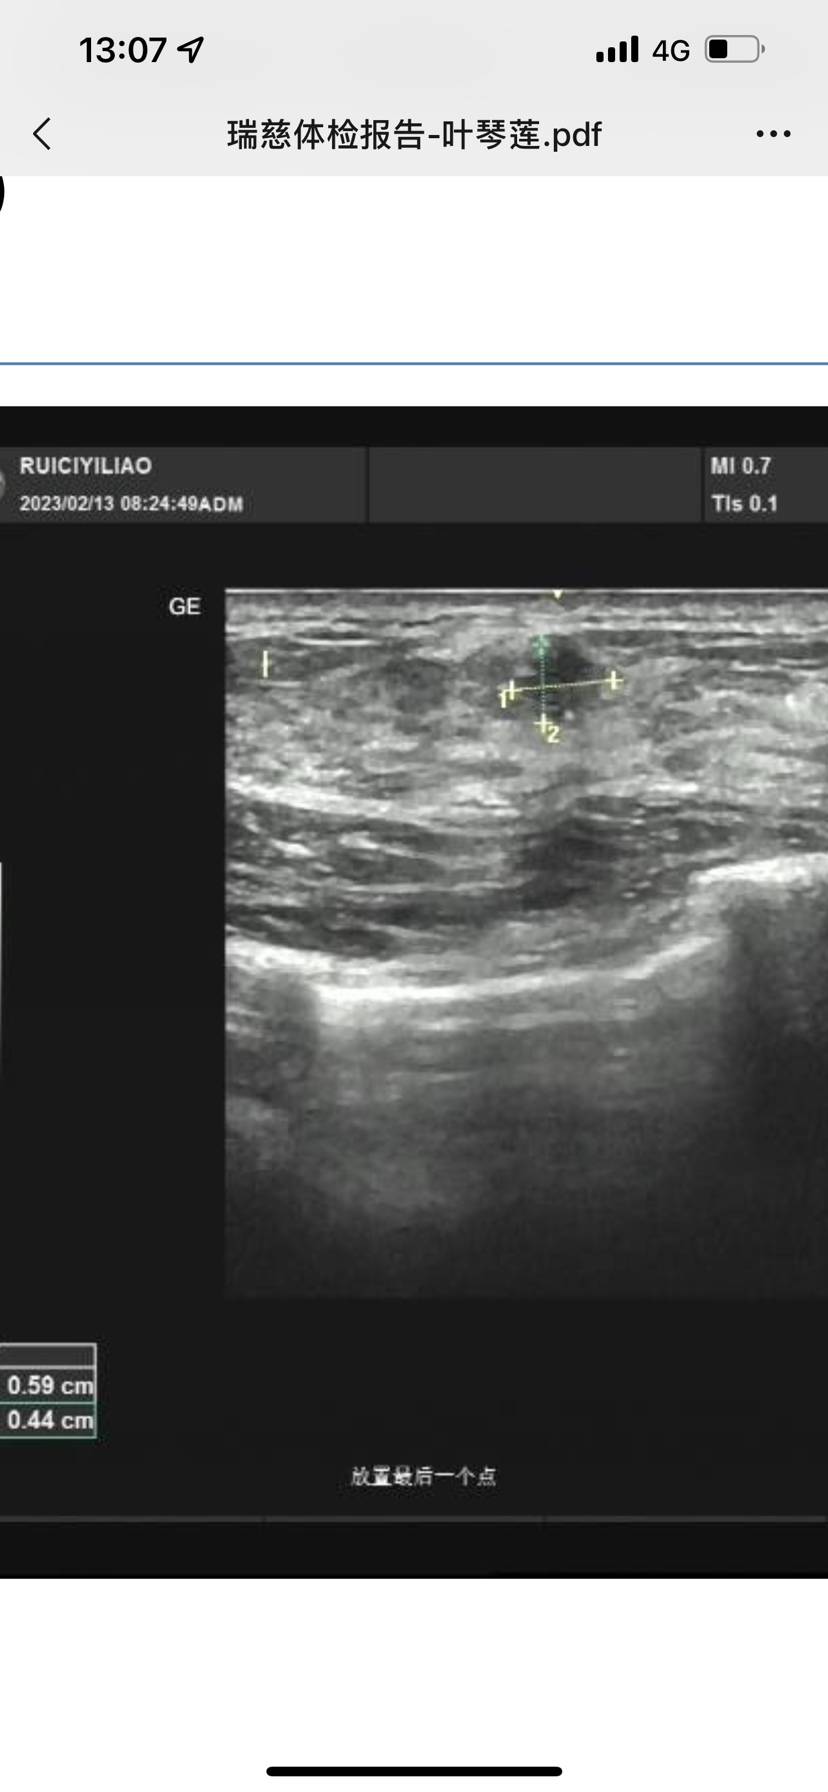

医生说左边的看着是恶性肿瘤 要马上给我做手术 ,左边是6*4mm 边界不清晰 形态不规则 底回声